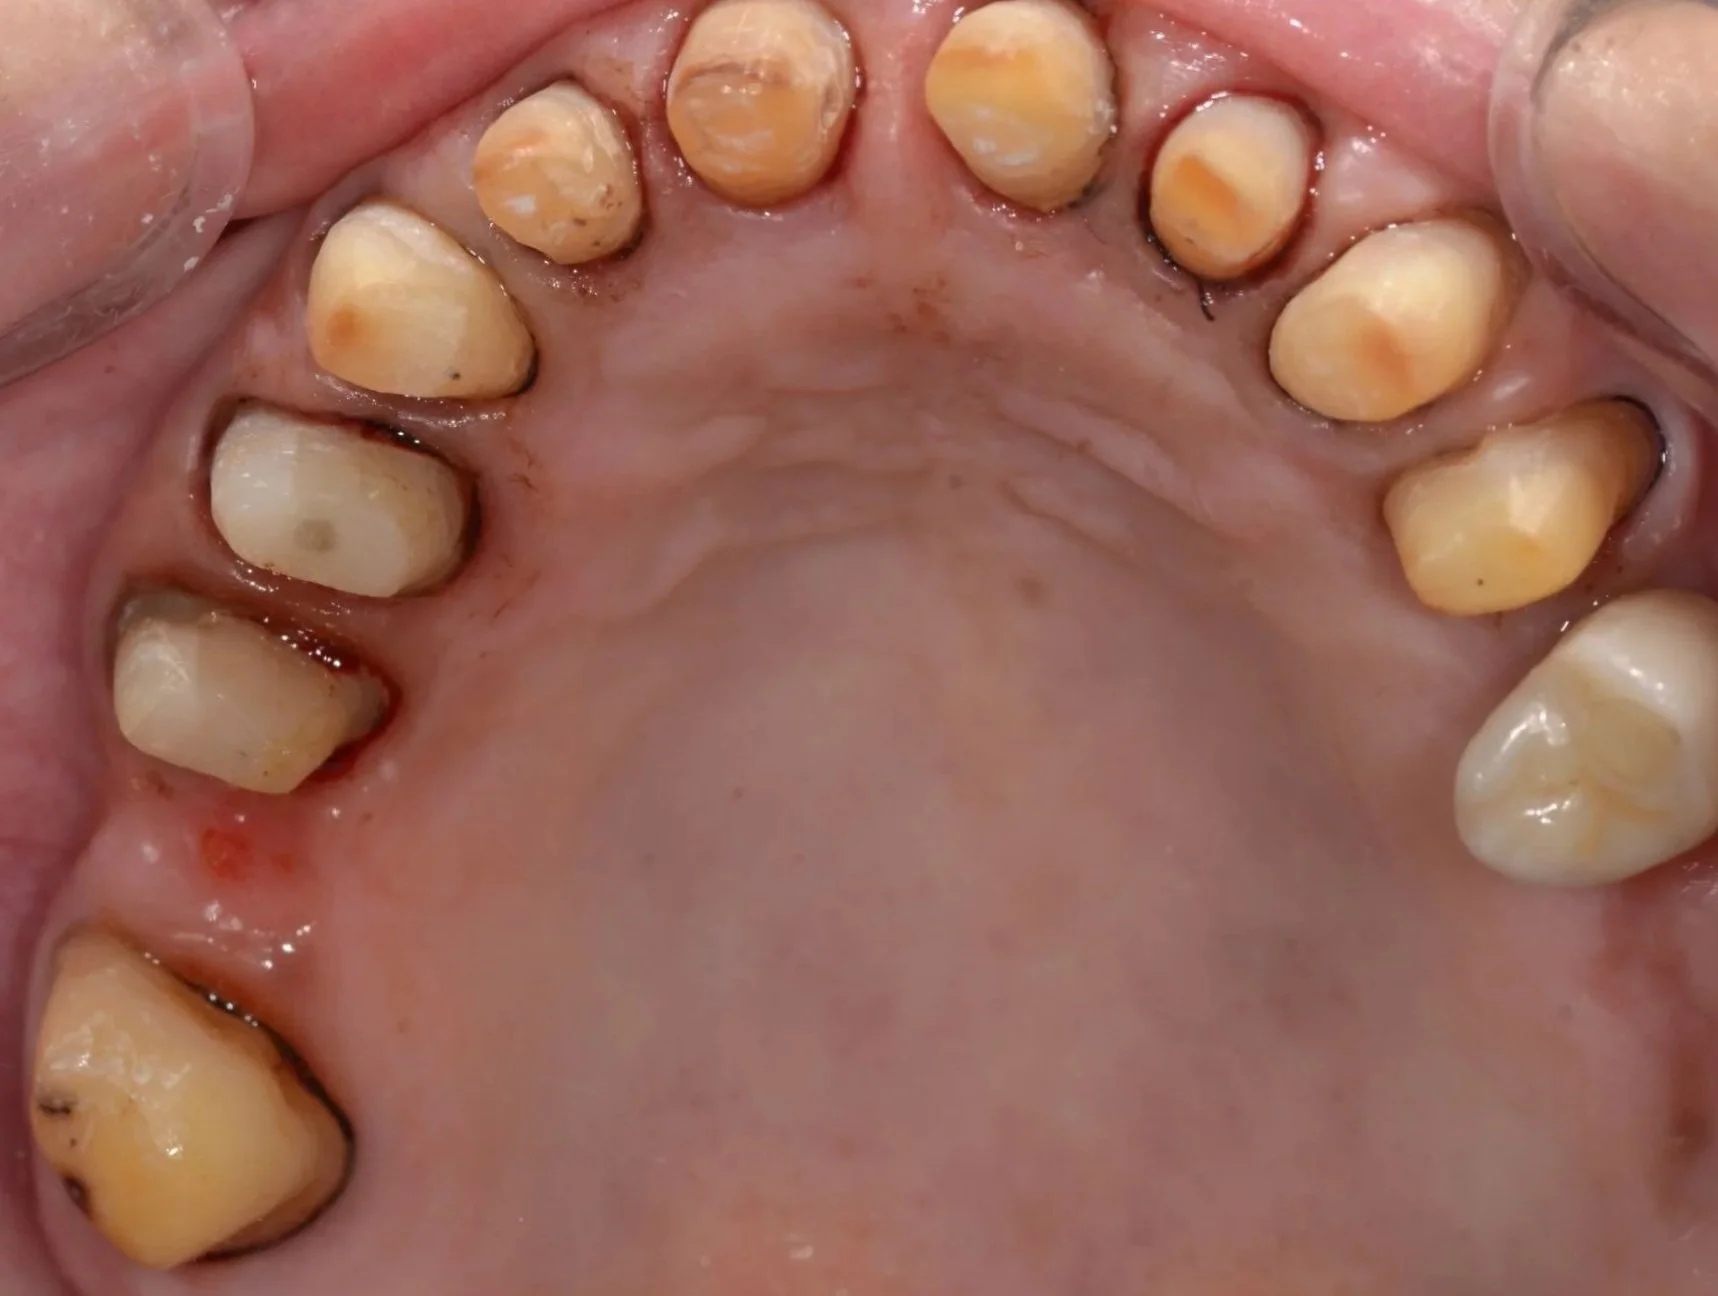

Diagnóstico: Riesgo y actividad de caries. Diagnóstico periodontal: Periodontitis estadio II grado A Generalizada. Diagnóstico oclusal: brechas desdentadas, plano quebrado por extrusión de molares superiores (17 y 27).

Inicial

Eliminación de caries y restauraciones

Tallados